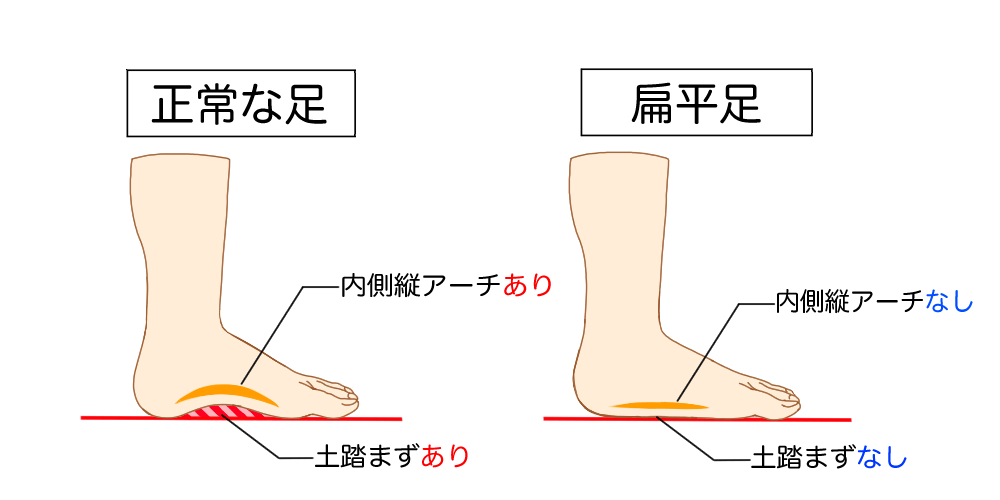

扁平足とは、足の病気の一つであり、多くの人が発症している可能性があります。扁平足は土踏まずがない(内側縦アーチと言われるアーチがなくなっている)状態であり、足の裏全面が地面についてしまうことを示しています。

最も簡単な方法が上記でも紹介した土踏まずがちゃんとあるかを確認することです。正しい足の状態では床などの上に立つと足裏の内側に空間ができます。空間が空いていれば正常な状態ですが、全く空間がなく、足裏全面が床に付いているのであれば扁平足の可能性が非常に高くなります。